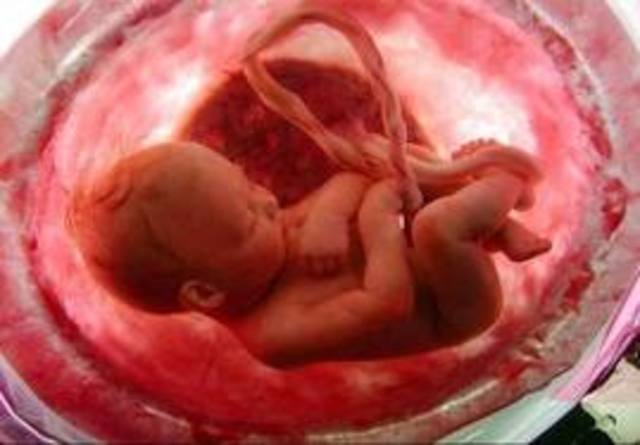

• ETAPA FETAL

ETAPA FETAL

9 SEMAMANS HASTA AL NACIMIENTO

*Capaz de responder a la estimulacion externa o interna.

*El fetro puede realizar algunos movimientos espontaneos.